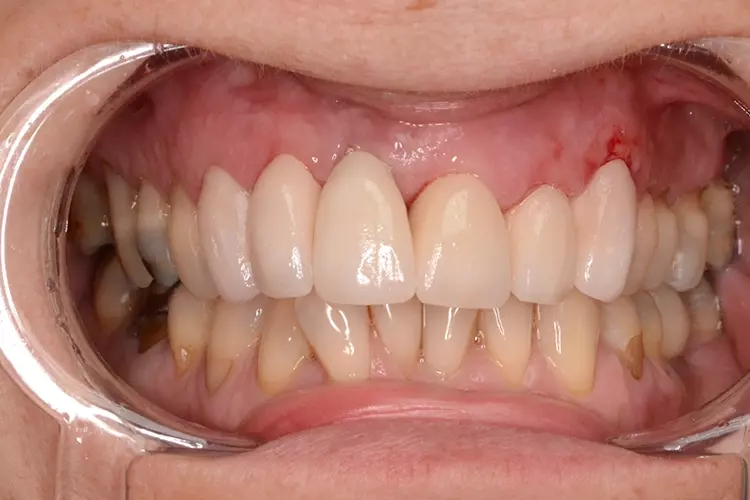

Neugestaltung der Front bei starken Zahnfehlstellungen

Bei dem heute 49-jährigen Patienten wurde seit Kindertagen versäumt, die Ober- und Unterkieferzahnbögen kieferorthopädisch auszurichten. Der Patient leidet seitdem stark unter seinen Zahnfehlstellungen.

Die Fraktur des stark elongierten Zahnes 21 war für den Patienten der Ausgangspunkt, sowohl die Front des Ober- als auch des Unterkiefers prothetisch überarbeiten zu lassen. Dabei wurde der frakturierte Zahn 21 durch ein navigiert eingesetztes Sofortimplantat ersetzt, während die verschachtelt stehenden Zähne 12 und 42 durch eine Brückenversorgung korrigiert wurden (Abb. 4a-j).